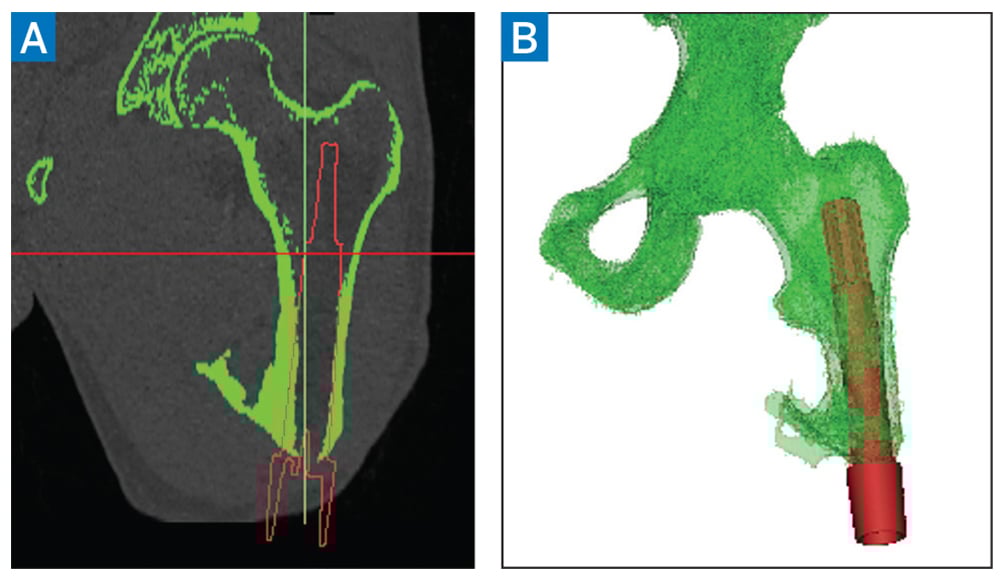

The patient underwent a transcutaneous osseointegration to implant a skeletally anchored prosthetic limb adapter, along with revision amputation of the heterotopic bone and a plastic surgery-assisted thigh lift to remove excess soft tissue. To prepare for this, preoperative computed tomography (CT) was performed to fabricate a custom titanium implant (Fig. 3).

Figure 3: Preoperative computed tomography scan. Initial renderings (A) allow volumetric reconstruction to model the patient-specific implant (B).